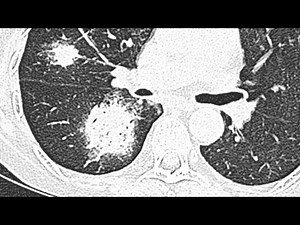

Halo Sign 的热门建议 |

in Head Injury - Halo

Symptoms - Halo